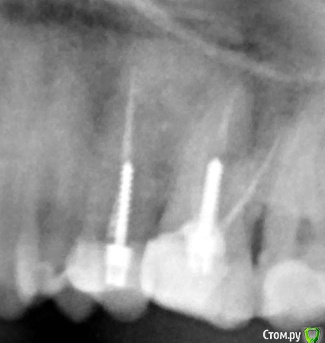

Помогите, пожалуйста, советом!В одной клинике были пролечены каналы и установлены анкерные штифты в 25,26 зубах.Зубы были восстановлены световыми пломбами с рекомендацией под коронки.С целью установки коронок обратились в другую клинику, где сначала сказали эти зубы перелечивать и ставить вкладки +коронки, но потом терапевт сказала, что при перелечивании есть большой риск того, что зубы пойдут на удаление и посоветовала накрыть коронками то, что есть..

Рисковать этими зубами не могу, поэтому пошла к ортопеду ,несмотря на дискомфорт в области этих зубов (терапевт сказала, что возможно это из-за давления пломб на дёсны..)После обточки и установки временных коронок, дискомфорт усилился и чувствую болезненные ощущения при надкусывании..Скажите, пожалуйста, по снимку( снимок до обточки) , нормально ли пролечены каналы, нет ли воспалений и как  правильнее поступить: ставить коронки на то, что есть или

необходимо всё же рисковать с перелечиванием?